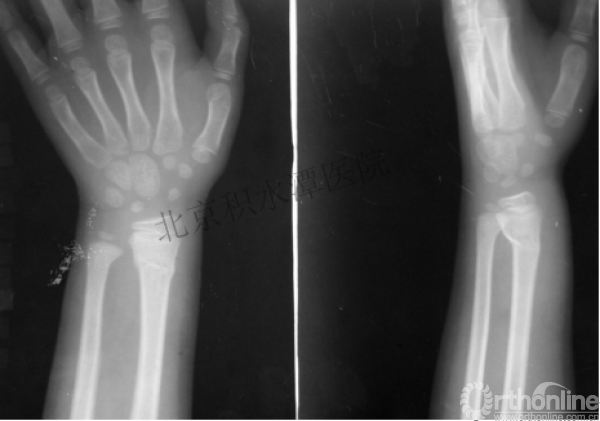

7岁、男孩,桡骨远端骨折

原始损伤片

手法整复后 - 45分钟!

伤后4天复查

伤后30天!

伤后40天—切开复位内固定!

伤后18个月